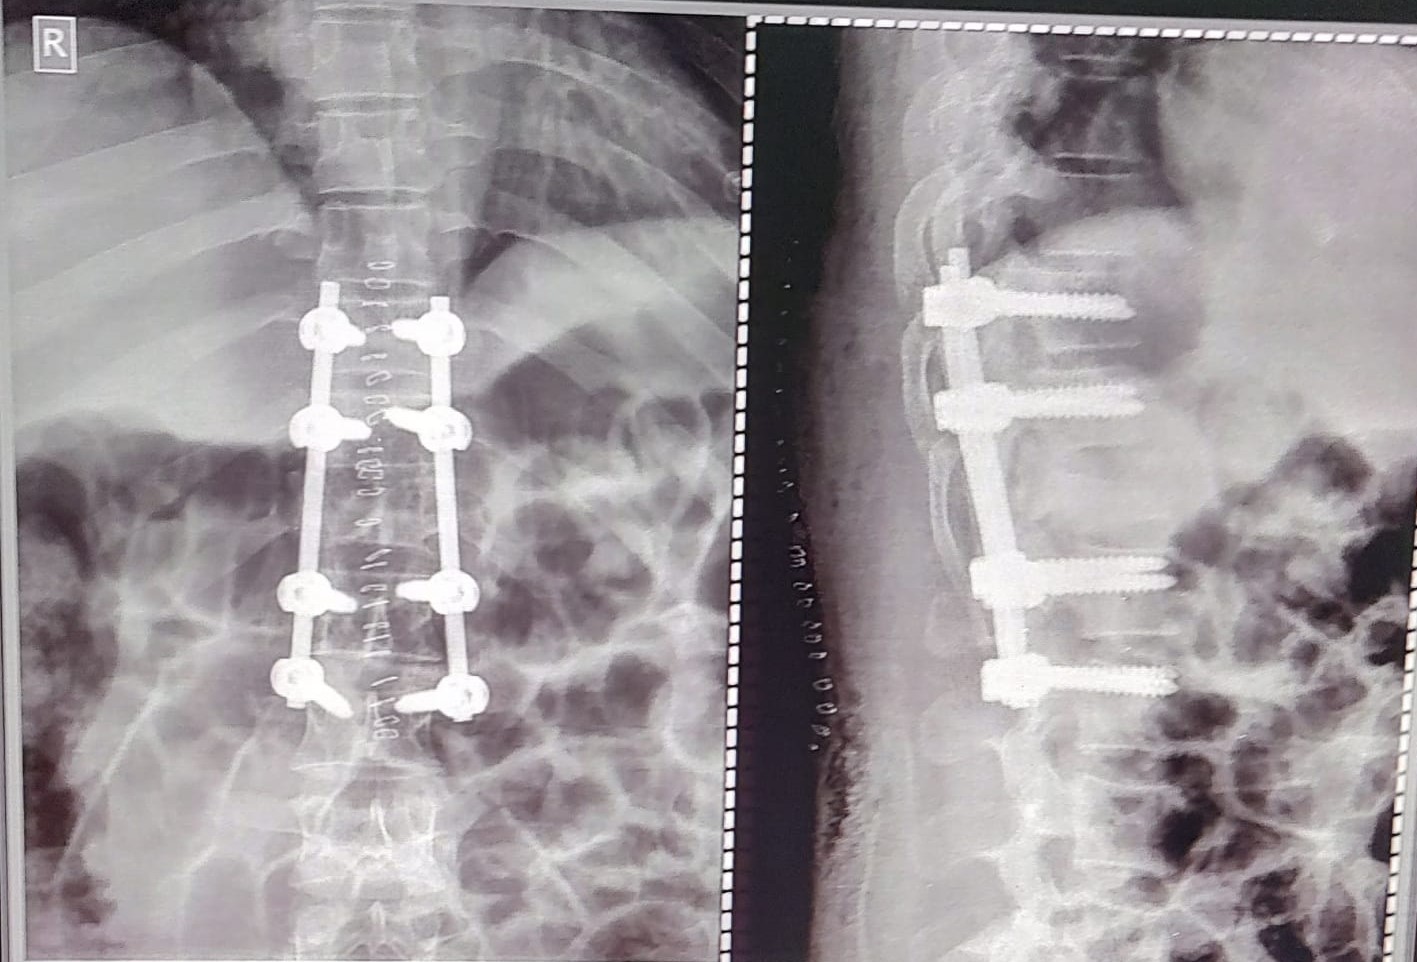

Spine Surgery